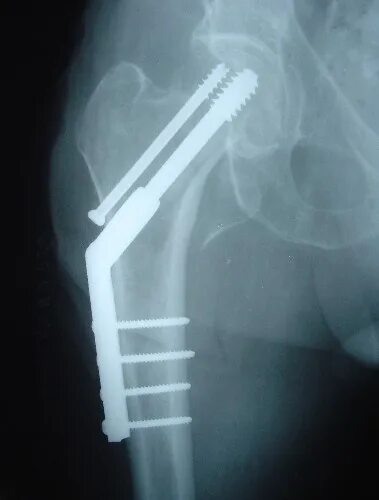

Остеосинтез чрезвертельного перелома